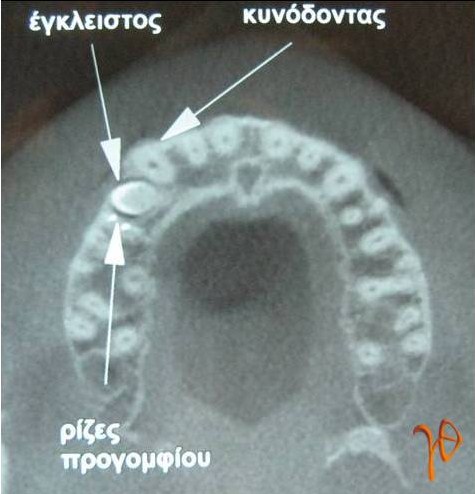

Εικ. 3 : Σε εγκάρσια τομή υπολογιστικής τομογραφία(CBCT) απεικονίζονται με ακρίβεια οι τοπογραφικές σχέσεις του υπεράριθμου με τα παρακείμενα δόντια.

Εικ. 11: Πανοραμική ακτινογραφία στην οποία απεικονίζεται ο υπεράριθμος προγόμφιος (βέλος) του 55-χρονου ασθενή. Παρότι ασυμπτωματικός, ο υπεράριθμός αφαιρέθηκε λόγω προγραμματισμού τοποθέτησης οδοντικών εμφυτευμάτων στην περιοχή.

Eικ. 12 : Διεγχειρητική εικόνα του υπεράριθμου προγομφίου της Περίπτωσης-3(βέλος), ο οποίος διχοτομήθηκε για τις ανάγκες της εξαγωγής (ένθετη φωτογραφία).

Για την Περίπτωση -3 κρατώ μια επιφύλαξη αν τεκμηριώνεται ως περίπτωση υπεράριθμου ή απλώς εγκλείστου προγομφίου. Από το οδοντιατρικό ιστορικό και την προσωπική συνεννόηση με τον θεράποντα οδοντίατρο, ο οποίος παρέπεμψε τον ασθενή, προκύπτει ότι πρόκειται για υπεράριθμο. Ωστόσο για την τεκμηρίωση θα έπρεπε να συμπεριλαμβάνεται και μια παλαιότερη ακτινογραφία της περιοχής.